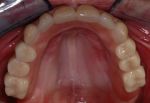

- Eingesetzte Teleskopprothese auf keramischen Primärkronen

Aufgrund der hohen Passgenauigkeit zwischen keramischen Primärkronen und galvanischen Sekundärkronen aus 99,99% Gold tritt keine Schaukelbewegung der Prothese ein. Sie wird wie fester Zahnersatz empfunden und wird wie eine Brücke gestaltet.

- Es ist keine Prothese mehr sondern eine herausnehmbare Brückenversorgung.